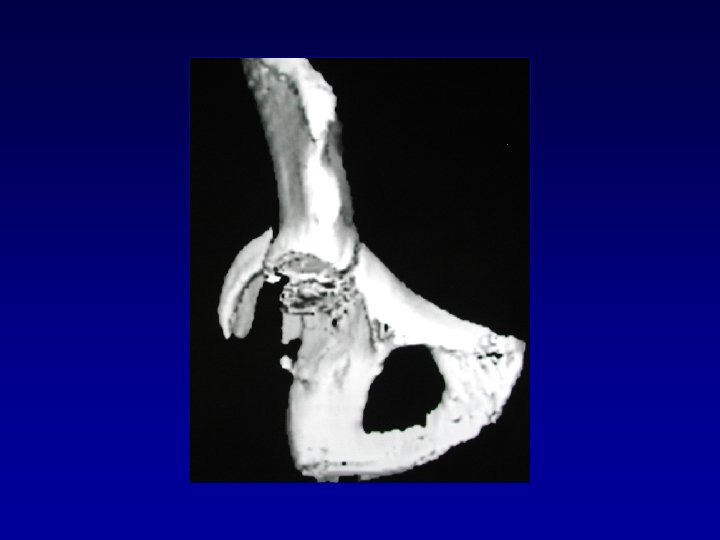

Déformation du cotyle • Ascensionné • Perte de substance osseuse scanner • Pseudarthrose •

Déformation du cotyle • Ascensionné • Perte de substance osseuse scanner • Pseudarthrose • Perte du positionnement exact (idem LCH) • Doit être reconstruit et recentré

Ostéome Problème majeur - Scanner • Difficultés chirurgicales • Risque neurologique • Récidive